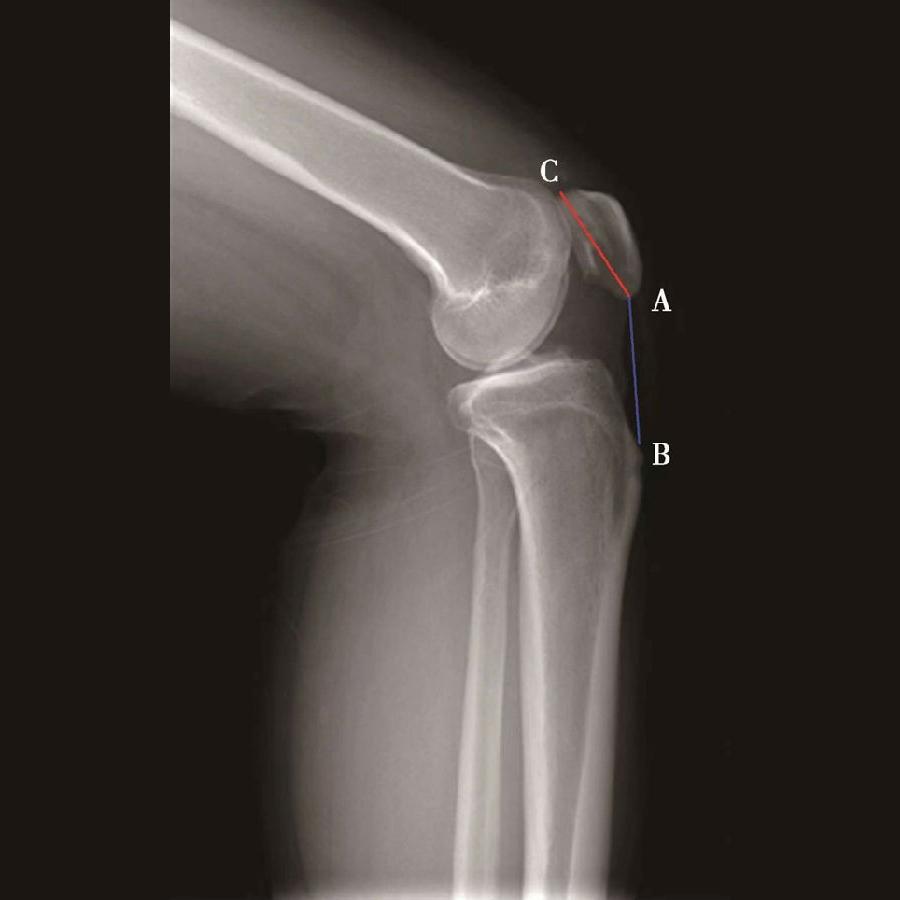

2️⃣ Insall-Salvati指数>1.2意味着高位髌骨(图5),<0.8意味着低位髌骨(图6)。

如图示:AB是髌韧带长度,AC髌骨纵轴长度。Insall-Salvati指数=AB/AC(图4)。

图5 Insall-Salvati指数=AB/AC=1.40,为高位髌骨

图6 Insall-Salvati指数=AB/AC=0.67,为低位髌骨